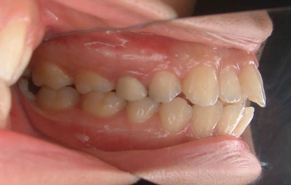

上下前歯のガタガタの症例です。ガタガタしている所は歯ブラシがとどかないので、茶色く着色しています。重なっている所は虫歯になっていることが、ほとんどです。

ガタガタの量が多く、物理的に顎の骨に入りきらないため、上下左右の前から4番目の歯(第一小臼歯)を抜いて、治療しました。抜かずに治療した場合、歯列の円周が広がり口元が突出してしまうため、抜歯をご選択されました。矯正後は歯磨きもし易く、歯の色も一緒にきれいになっています。